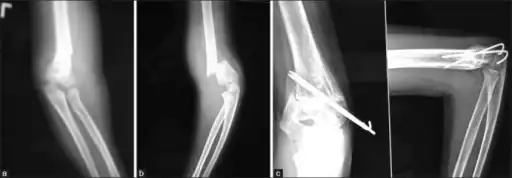

Percutaneous pinning

Percutaneous pinning are usually inserted over the medial or lateral sides of the elbow under X-ray image intensifier guidance. There is 1.8 times higher risk of getting nerve injury when inserting both medial and lateral pins compared to lateral pin insertion alone. However, medial and lateral pins insertions are able to stabilise the fractures more properly than lateral pins alone. Therefore, medial and lateral pins insertion should be done with care to prevent nerve injuries around elbow region.[3]

Percutaneous pinning should be done when close manipulation fails to achieve the reduction, unstable fracture after closed reduction, neurological deficits occurs during or after the manipulation of fracture, and surgical exploration is required to determine the integrity of the blood vessels and nerves. In open fractures, surgical wound debridement should be performed to prevent any infection into the elbow joint. All Type II and III fractures requiring elbow flexion of more than 90° to maintain the reduction needs to be fixed by percutaneous pinning. All Type IV fractures of supracondylar humerus are unstable; therefore, requires percutaneous pinning. Besides, any polytrauma with multiple fractures of the same side requiring surgical intervention is another indication for percutaneous pinning.[3]